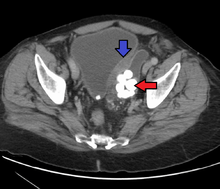

Urothelial carcinoma (UCC, also transitional cell carcinoma or TCC) is a type of cancer that typically occurs in the urinary system: the kidney, urinary bladder, and accessory organs. It is the most common type of bladder cancer and cancer of the ureter, urethra, and urachus. It is the second most common type of kidney cancer, but accounts for only five to 10 percent of all primary renal malignant tumors.

TCCs are often multifocal, with 30–40% of patients having more than one tumor at diagnosis. The pattern of growth of TCCs can be papillary, sessile (flat) or carcinoma-in-situ (CIS).

The most common site of TCC metastasis outside the pelvis is bone (35%); of these bone metastases, 40 percent are in the spine.[3]